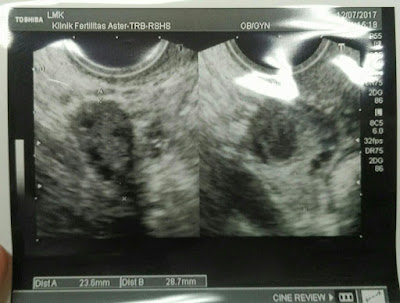

Giliran saya dipanggil untuk USG Transvaginal. Dengan di dampingi oleh Suster Meri, Dokter Mulya melakukan pemeriksaan. Dan saat saya ditunjukkan layar USG, saya senyum sumringah kegirangan. Karena di USG yang kedua kalinya sejak 1 minggu lalu, saya fix dinyatakan sudah sembuh dari PCOS! Sama sekali tidak terlihat sel telur berantai anggur lagi, yang ada justru saya mendapat kejutan manis, bahwa ada 2 sel telur besar & sudah pecah di kanan & kiri!

Seketika Dokter Mulya nyeletuk sembari tersenyum renyah dan menunjukkan gambaran sel telur saya, "Ini sel telur kanan, dan ini yang kiri ya Lana, kalau jadi dua-duanya (bulan ini berhasil), bisa kembar nih....bisa kembar 3".hehehe....

| Gambaran Sel telur kiri & kanan. Menurut Dokter, Kedua sel telur saya besar & sudah pecah. |